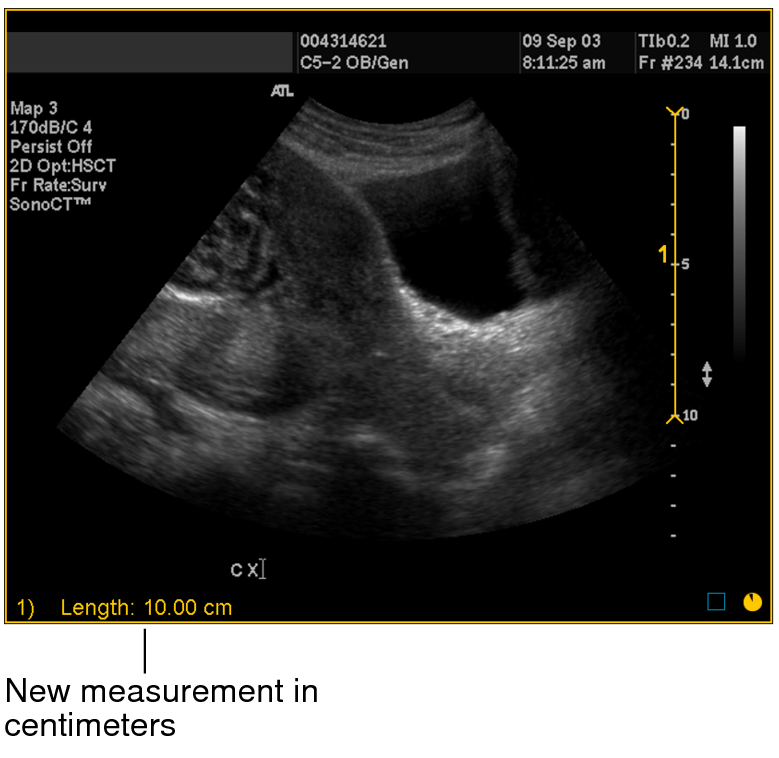

The image is calibrated and the length of the measurement now appears in centimeters. All subsequent linear, orthogonal, elliptical, and freehand region of interest measurements that you create on the image are calibrated according to this ratio.

New measurement